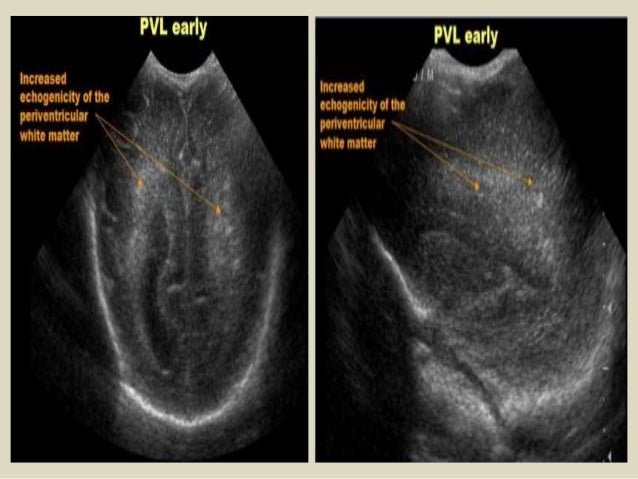

21. 21. Peri Ventricular Leukomalacia (PVL) PVL is also known as Hypoxic-Ischemic Encephalopathy (HIE) of the preterm. It is a white matter disease that affects the periventricular zones. In prematures this white matter zone is a watershed zone between deep and superficial vessels. Until recently ischemia was thought to be the single cause of PVL, but probably other causes (infection, vasculitis) play an additional role. PVL presents as areas of increased periventricular echogenicity. Normally the echogenicity of the periventricular white matter should be less than the echogenicity of the choroid plexus. PVL occurs most commonly in premature infants born at less than 33 weeks gestation (38% PVL) and less than 1500 g birth weight (45% PVL). Detection of PVL is important because a significant percentage of surviving premature infants with PVL develop cerebral palsy, intellectual impairment or visual disturbances. More than 50% of infants with PVL or grade III hemorrhage develop cerebral palsy.

22. 22. Sagittal image of a child with PVL grade 1.

23. 23. Transverse and sagittal image of a child with PVL grade 2.

24. 24. Sagittal and coronal images demonstrating extensive PVL grade 3

25. 25. Coronal and transverse images demonstrating PVL grade 4.

26. 26. Coronal and transverse images demonstrating PVL grade 4.